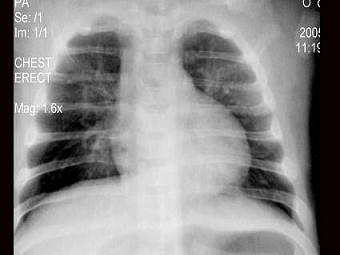

问题 女,1岁半,发热伴咳嗽5天,如图所示,最可能的诊断为?(?)

选项 A.支气管炎 B.肺门结核 C.支气管肺炎 D.肺隔离症 E.以上均不正确

答案 C